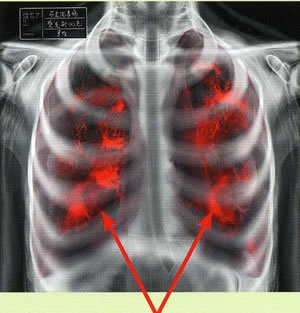

Для выявления патологических процессов на ранних стадиях проводятся профилактические медицинские осмотры на производстве. Выполняется рентгенодиагностика легких. Ряд исследовательских тестов на определение функции внешнего дыхания облегчают постановку диагноза. К ним относится спирометрия, пикфлоуметрия, пневмотахография, газоанализ внешнего дыхания. Много информации дают компьютерная томография и МРТ легких.

Методы лучевой диагностики имеют вспомогательное значение. Специфичных для биссиноза рентгенологических признаков не существует. Рентгенография и КТ органов грудной клетки помогают обнаружить наличие бронхоэктазов, эмфиземы и других лёгочных осложнений. Определение общего и специфического IgЕ, прик-тесты позволяют выявить сенсибилизацию к пыльце, продуктам питания, бытовым и эпидермальным аллергенам и отличить биссиноз от бронхиальной астмы. Степень поражения правых отделов сердца определяется с помощью эхокардиографии.

- рентгенография;

Определяется четкая взаимосвязь симптомов с трудовой деятельностью, что позволяет установить характер профессионального заболевания. Классическими проявления биссиноза является «синдром понедельника». Ранее выявления заболевания проводится посредством анкетирования. Уточнить диагноз и дифференцировать биссиноз с другой бронхолегочной патологией позволяют такие методы исследования, как спирометрия, пикфлоуметрия, рентгенография и компьютерная томография органов грудной клетки. Также в диагностических целях больному может быть назначено определение общего и специфического IgЕ, прик-тесты и эхокардиография.

Рентгенологические проявления. Характерных рентгенологических проявлений нет. Это находится в противоречии с большинством других видов пневмокониоза, при которых рентгенологические проявления часто на несколько лет опережают функциональные нарушения. При биссинозе функциональные нарушения — самое раннее проявление заболевания, и было показано, что, даже если симптомы не прогрессируют, FEV снижается после контакта с пылью в первый день работы после перерыва [177].

Биссиноз — пример по преимуществу того, как функция легких соответствует наличию профессионального заболевания легких, тогда как рентгенологические данные обычно нормальны.

Оценка

Нет известных диагностических тестов на биссиноз. Однако острое воздействие хлопковой пыли может привести к серологическому увеличению числа лейкоцитов. Диагноз часто затруднен, потому что состояние может имитировать астму и многие другие пневмокониозы. Помимо физического осмотра, который не является специфическим, требуется рентген грудной клетки для исключения других патологий. Самый большой ключ к заболеванию заключается в том, что пациент обычно жалуется на то, что симптомы ухудшаются, когда он или она приходит на работу в понедельник (отсюда и название болезнь понедельника ), и улучшаются, когда он не работает.

У небольшой части пациентов при физикальном обследовании обнаруживались мелкие базилярные хрипы.[11] Рентгенологическое исследование показало наличие гиперлюминесценции, уплощения диафрагмы и эмфиземы [6]. Также наблюдалась диффузная, нечеткая мутность, преимущественно в нижних отделах легких. КТ грудной клетки обычно проводится, когда диагноз неясен или когда нужно исключить другие заболевания.

Доступная литература по рентгенологическим данным ограничена, однако сообщалось о помутнениях по типу матового стекла, распределенных в основном базальным образом с центрилобулярными узелками на КТВР.[12]